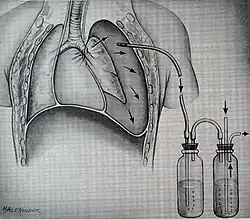

The term blunt thoracic trauma, or, more informally, blunt chest injury, encompasses a variety of injuries to the chest. Broadly, this also includes damage caused by direct blunt force (such as a fist or a bat in an assault), acceleration or deceleration (such as that from a rear-end automotive crash), shear force (a combination of acceleration and deceleration), compression (such as a heavy object falling on a person), and blasts (such as an explosion of some sort). Common signs and symptoms include something as simple as bruising, but occasionally as complicated as hypoxia, ventilation-perfusion mismatch, hypovolemia, and reduced cardiac output due to the way the thoracic organs may have been affected. Blunt thoracic trauma is not always visible from the outside and such internal injuries may not show signs or symptoms at the time the trauma initially occurs or even until hours after. A high degree of clinical suspicion may sometimes be required to identify such injuries, a CT scan may prove useful in such instances. Those experiencing more obvious complications from a blunt chest injury will likely undergo a focused assessment with sonography for trauma (FAST) which can reliably detect a significant amount of blood around the heart or in the lung by using a special machine that visualizes sound waves sent through the body. Only 10–15% of thoracic traumas require surgery, but they can have serious impacts on the heart, lungs, and great vessels.[12]

The most immediate life-threatening injuries that may occur include tension pneumothorax, open pneumothorax, hemothorax, flail chest, cardiac tamponade, and airway obstruction/rupture.[12]

The injuries may necessitate a procedure, most commonly the insertion of an intercostal drain, or chest tube. This tube is typically installed because it helps restore a certain balance in pressures (usually due to misplaced air or surrounding blood) that are impeding the lungs' ability to inflate and thus exchange vital gases that allow the body to function.[13] A less common procedure that may be employed is a pericardiocentesis, which, by removing blood surrounding the heart, permits the heart to regain some ability to appropriately pump blood.[14][15] In certain dire circumstances an emergent thoracotomy may be employed.[16]

Treatment of blunt thoracic trauma

Nine out of ten patients with thoracic trauma can be treated effectively without a surgical operation.[37] If surgery is indicated, there are numerous options available. A comprehensive discussion between the patient and the surgeon will take place to carefully evaluate the best approach, tailored to the patient's specific condition and injury. Conservative measures such as maintaining a clear and open airway, oxygen support, tube thoracostomy, and volume resuscitation are often given to manage blunt thoracic trauma.[37] Oftentimes, pain control is the most basic and effective treatment approach because the presence of severe pain may lead to impairment of proper breathing, further exacerbating impaired lungs.[37] Pain management in thoracic trauma patients improves the ability to breathe properly on their own, encourages the excretion of pulmonary secretions, and decreases the aggravation of inflammation and low oxygen levels in the blood.[37] Nonsteroidal anti-inflammatory drugs, opioids, or regional pain management methods, such as local anesthetic, can be used for pain control.[37]